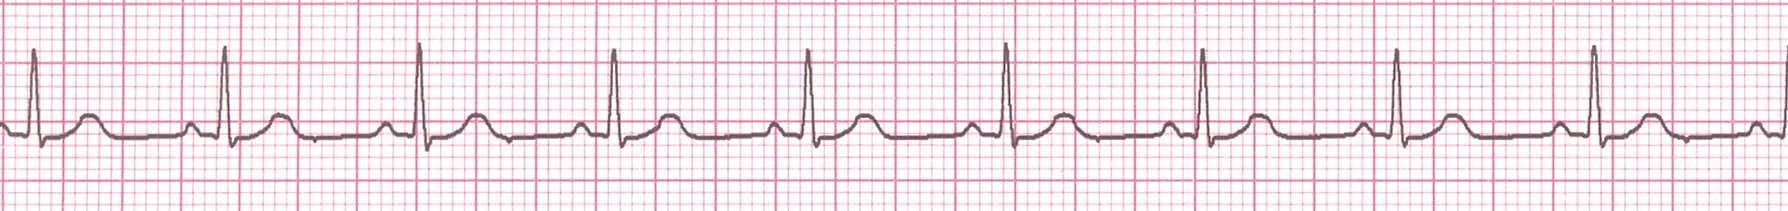

Putting It All Together

Do you think this person is having a myocardial infarction. If so, where?

Yes, this person is having an acute anterior wall myocardial infarction.